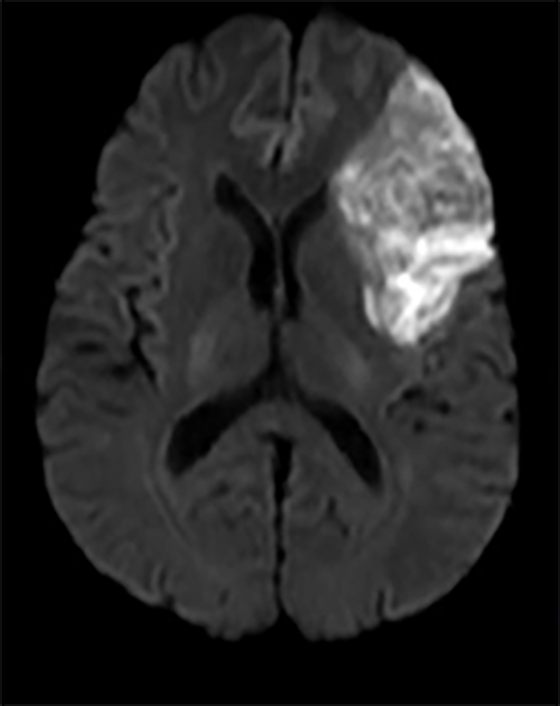

Deși unele tipuri de infarct sunt aparente pentru ochiul liber neprofesionist (Fig.2), altele sunt mai subtile și mult mai reduse în intensitatea aparentă și dimensiune (Fig.3 & Fig.4).

În imaginile din figurile 2-4 se pot vedea cu ochiul liber abnormalitățile la nivelul creierului din imaginile RMN. Astfel de cazuri reprezintă o parte importantă din setul de date, iar restul imaginilor e compus din cazuri mult mai greu de identificat sau clasificat chiar și pentru radiologii cu experiență. Pentru moment suntem departe de a concura cu precizia și acuratețea radiologilor, dar soluțiile de detecție automată de astfel de leziuni vor să vină în ajutorul medicilor. Un medic radiolog interpreta în jur de 679 imagini de tip RMN per zi în anul 2010 [9]. De atunci cantitatea de imagini produse de aparatura medicală e în continuă creștere iar presiunea asupra radiologilor crește și ea, iar cu aceasta cresc și șansele de eroare sau de ratare a unor leziuni importante. O soluție automată vine ca un adjuvant pentru radiolog asigurându-se că acestuia nu îi scapă niciun caz clar de leziune, iar radiologul se poate axa pe cazurile cu adevărat dificile și importante. Și în plus, un algoritm nu suferă de oboseală și nici nu necesită repaus.

Fig. 2 a) Simulare detecție de infarct cerebral acut din RMN-DWI. Ref: [6]